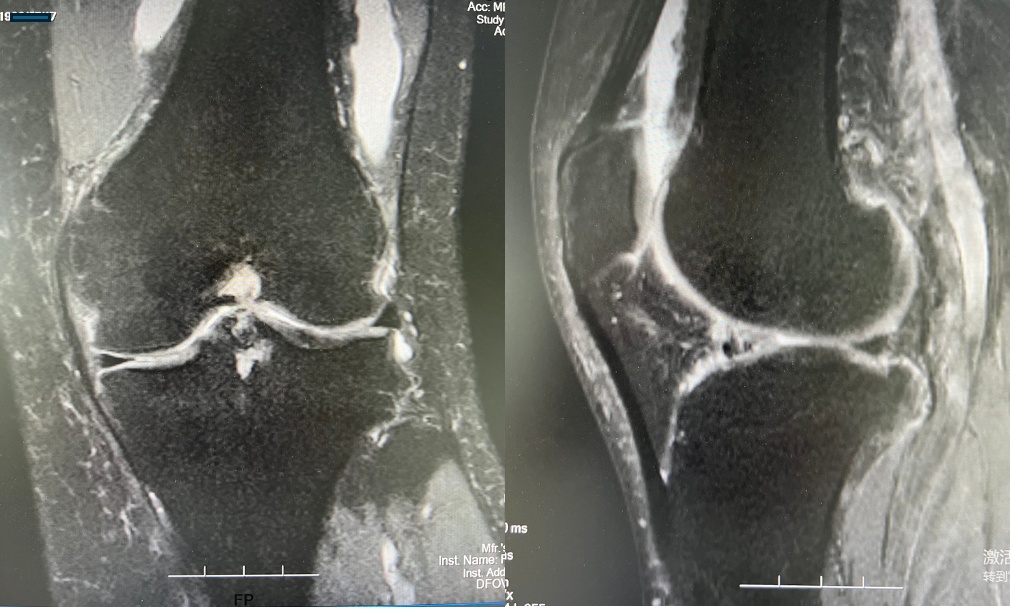

经核磁检查

小王的膝关节积液,关节软骨骨挫伤

经医生询问得知

原来,这段时间小王刚接触骑行

每天都骑行很长时间

结果出现了关节疼痛肿胀的现象